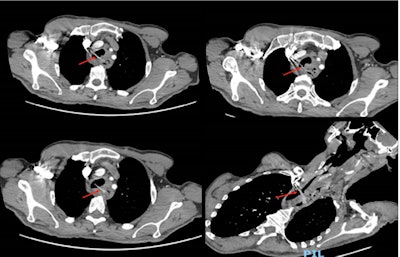

Axial slices of the computed tomography scan with contrast. Images show a linear hyperdense shadow extending from the esophagus to the proximal trachea within a tracheo-esophageal fistulous tract at the level of T2 vertebrae.